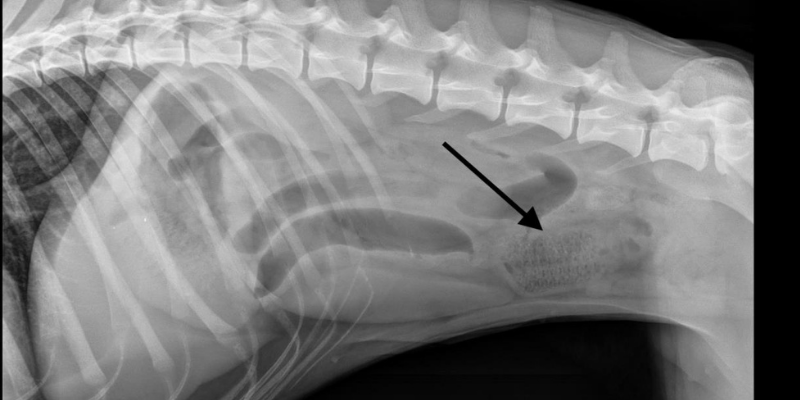

An x-ray of a foreign body – a corn cob that a dog ate!

Do you do foreign body surgery where you take things out of pets that they ate that they shouldn’t have?

Dr. Anderson: Do I!? Seems like constantly! This is a pretty common surgery we do at AERC. Typically, it’s a young dog who ate or swallowed something they shouldn’t – it might be a chew toy or something covered in bacon grease. They swallow it, it tasted good, and then it will travel down their intestine and it won’t quite fit. It will get obstructed, everything backs up. Your pet will stop eating, start vomiting, & overall, not feel well.

If a pet like that comes into AERC, on the exam, they are also dehydrated and have abdominal pain. So, when we gently feel their belly – they’ll give us subtle signs that ‘hey, that doesn’t feel good’. The pet will then get x-rays where we can see patterns within the intestines that tell us there is an obstruction. We use that information to make a recommendation to go to surgery.